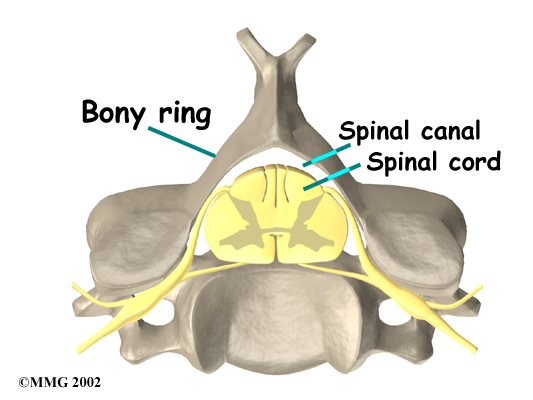

Each vertebra is formed by a round block of bone, called a vertebrae body. A bony ring attaches to the back of the vertebral body. When the vertebrae are stacked on top of each other, the rings form a hollow tube. This bony tube surrounds the spinal cord as it passes through the spine. Just as the skull protects the brain, the bones of the spinal column protect the spinal cord.

Vertebrae Body

Bony Ring

Bony Ring

As the spinal cord travels from the brain down through the spine, it sends out nerve branches between each vertebrae called nerve roots. These nerve roots join together to form the nerves that travel throughout the body and form the body's electrical system. The nerve roots that come out of the cervical spine form the nerves that go to the arms and hands. The thoracic spine nerves go to the abdomen and chest. The nerves coming out of the lumbar (lower) spine go to the organs of the pelvis, the legs, and the feet.